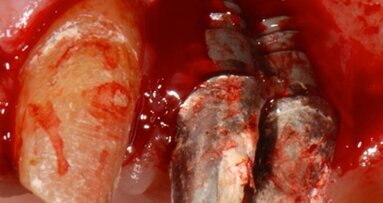

Dopo 9 mesi, è stata eseguita una seconda CBCT per valutare il volume di osso rigenerato e per pianificare la chirugia computer guidata (Fig. 23); i file .STL ottenuti dalla scansione 3D e i files .DICOM della CBCT sono stati utilizzati per pianificare l’inserimento degli impianti tramite una chirurgia computer guidata (Navimax, Biomax) (Fig. 24) . Il giorno della chirurgia implantare (T1), è stata eseguita un’incisione orizzontale para-crestale, per permettere l’esposizione della griglia e la sua rimozione, previa rimozione delle viti in titanio e dell’osso formatosi al di sopra di essa (Figg. 25, 26). L’esame clinico ha evidenziato una completa rigenerazione ossea del difetto osseo verticale, con assenza di pseudo-periostio o pseudo-periostio minore di 1 mm, di conseguenza pseudo-periostio di “classe 1” secondo la classificazione di Cucchi et al.20 (Figg. 27, 28). Successivamente, la dima chirurgica è stata posizionata e fissata nella posizione pianificata; i siti implantari sono stati preparati con frese progressive dedicate; e tre impianti conici (T3, Zimvie) sono stati inseriti nelle posizioni #15, #16 e #17, secondo la pianificazione protesicamente guidata eseguita precedentemente mediante il software da chirurgia guidata (Figg. 29-31). Gli impianti sono stati “sommersi”, attendendo la corretta osteointegrazione, ed è stata eseguita una chiusura per prima intenzione (Fig. 32). Dopo il posizionamento degli impianti, è stata eseguita una radiografia OPT (Fig. 33).